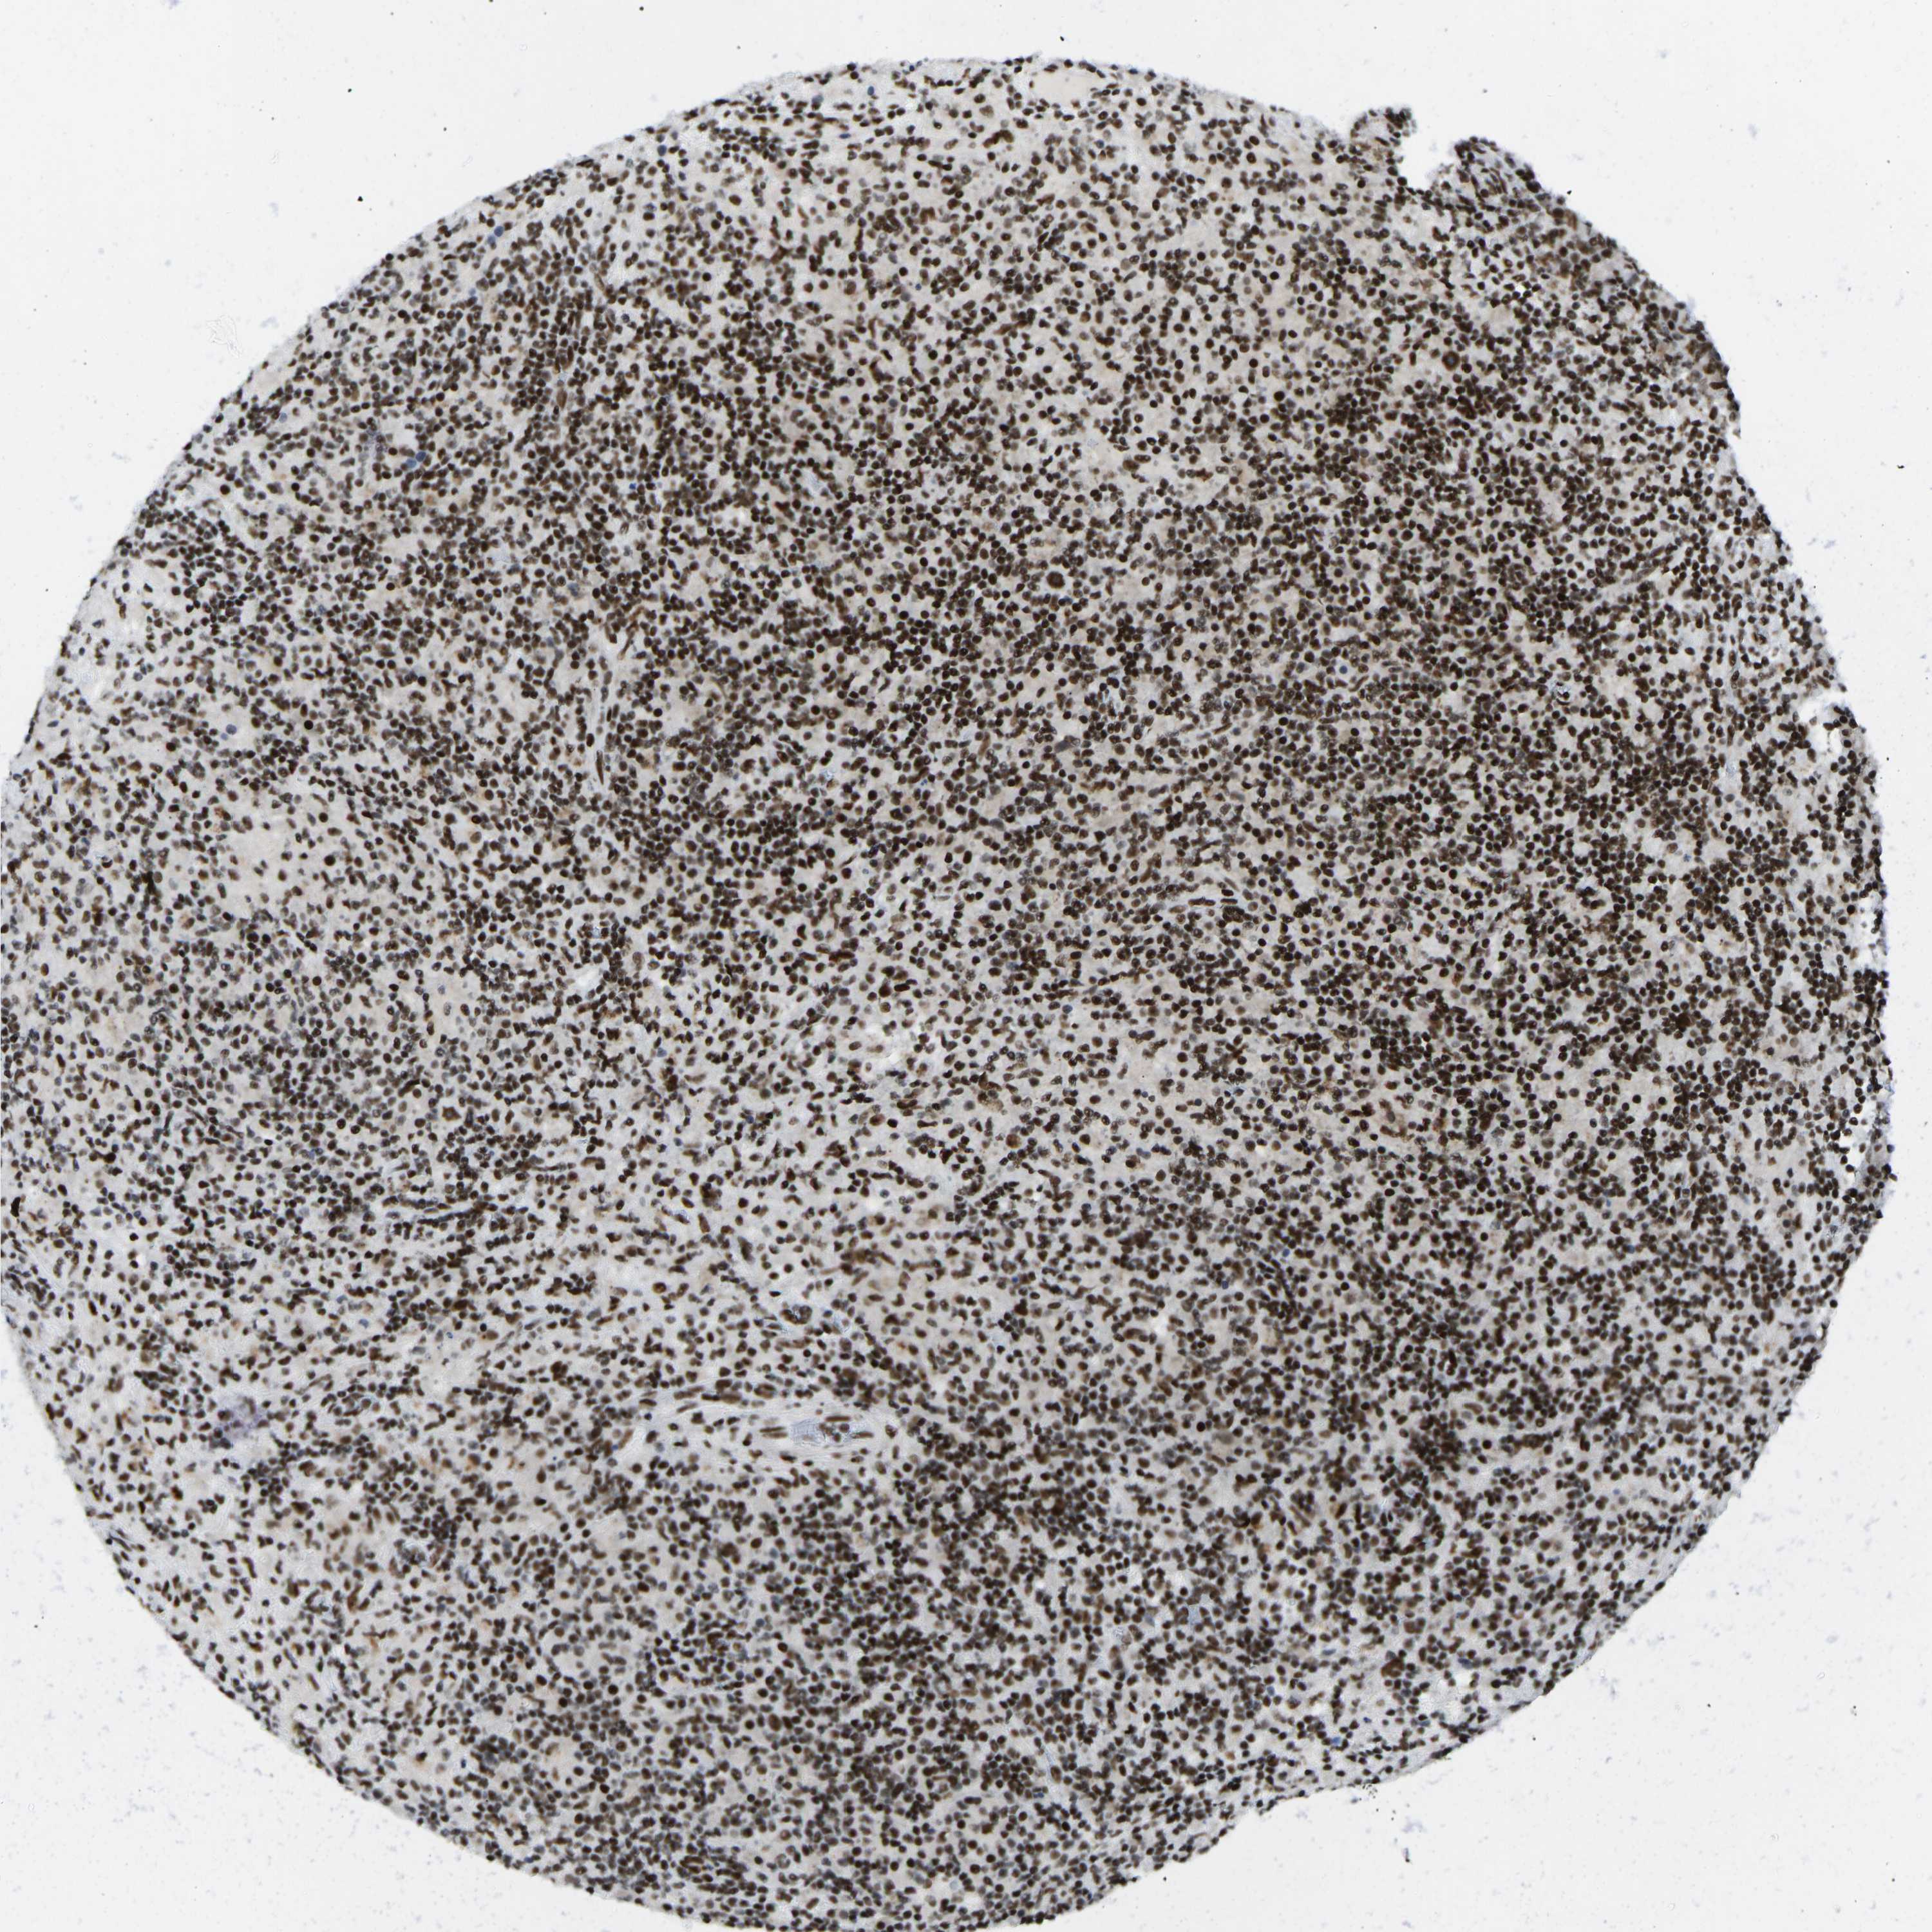

CANCER LYMPHOMA Show tissue menu

LYMPHOMA - Protein expressioni

A mouse-over function shows sample information and annotation data. Click on an image to view it in a full screen mode. Samples can be filtered based on level of antibody staining by selecting one or several of the following categories: high, medium, low and not detected. The assay and annotation is described here.

Each image is clickable and will lead to virtual microscopy that enables deeper exploration of all samples and also displays staining intensity scores, fraction scores and subcellular localization as well as patient and tissue information for each sample.

Antibody HPA018864

Hodgkin's disease, NOS

Malignant lymphoma, non-Hodgkin's type, High grade

Malignant lymphoma, non-Hodgkin's type, Low grade